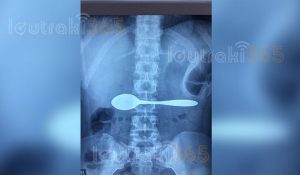

Η 35χρονη, τους εξήγησε ότι καταλάθος, κατάπιε ένα κουτάλι. Οι γιατροί του Νοσοκομείου, της είπαν να βγάλει αμέσως ακτινογραφία για να διαπιστώσουν αν όσα έλεγε η Κορίνθια ασθενής, ανταποκρίνονταν στην πραγματικότητα.

Και όμως. Μόλις η ακτινογραφία επιβεβαίωσε τα όσα έλεγε η 35άχρονη, οι γιατροί του Νοσοκομείου Κορίνθου την έστειλαν αμέσως σε εφημερεύον Νοσοκομείο της Αθήνας, καθώς έπρεπε να εξετασθεί από γαστρεντερολόγο που δεν υπήρχε στο Νοσοκομείο Κορίνθου.